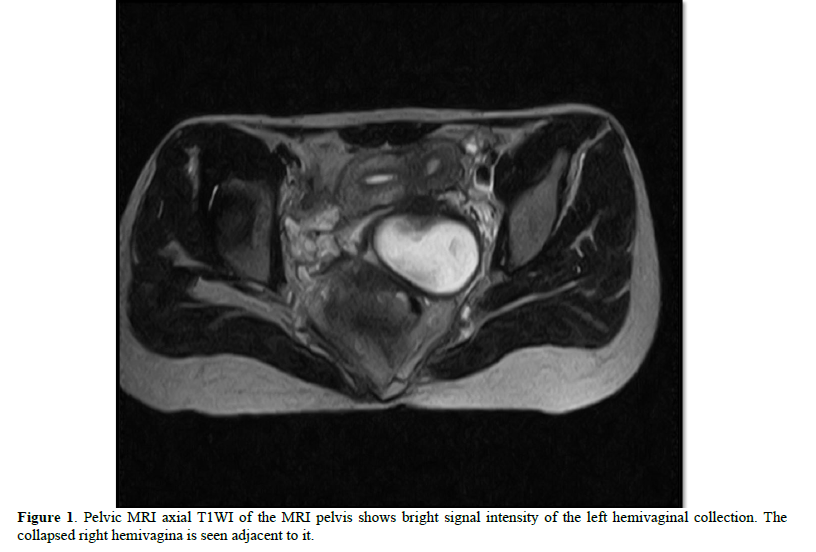

18 year’s old unmarried female was admitted in our casualty with complaints of acute abdomen. Acute onset in pain which was moderate in intensity, continuous without any relieving or aggravating factors mainly localized in the lower abdomen and associated with vomiting. Her previous menstrual cycle was 3-4/28-30 days with complaints of dysmenorrhea and LMP was two weeks back. She was stable and there was no pallor. Her pulse was 84 bpm, BP- 110/80 mmHg, RR- 20/min. On examination, there was slight tenderness and an ill-defined mass felt in left iliac fossa with rebound tenderness. On speculum examination, cervix was flushed with vagina; bulge is seen right vaginal wall. A cystic non-tender mass felt in right fornix with restricted mobility projecting in vagina on bimanual examination. So, possibility of appendicular lump or left TO mass was kept. Blood investigations were normal. Urine pregnancy test (UPT) was negative. Transabdominal ultrasonography showed septated uterus, cervix and vagina with non-visualization of left kidney. A cystic mass showing internal echoes on the left side of vagina and a septate uterus with blood in the cavity was noted. On MRI abdomen and pelvis, a complete septate uterus with haematocolpus of left hemivagina with absent left kidney and solitary right kidney showing hypertrophy was noted i.e., OHVIRA syndrome (Figures 1-3).